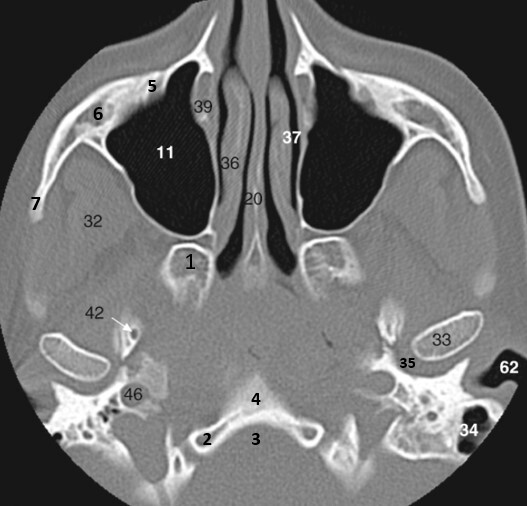

20

Label 36,37,46,62

A

36=Rt. Inferior nasal concha

37=Lt. Inferior nasal meatus

46=Lt. carotid canal

62= Lt. EAM

19

Label 7,20,32,33,34

7=Rt Zygomatic arch

20=Nasal septum (Vomer)

32=Right Temporalis muscle

33=Lt condyloid process (mandible)

34=Left Mastoid air cells